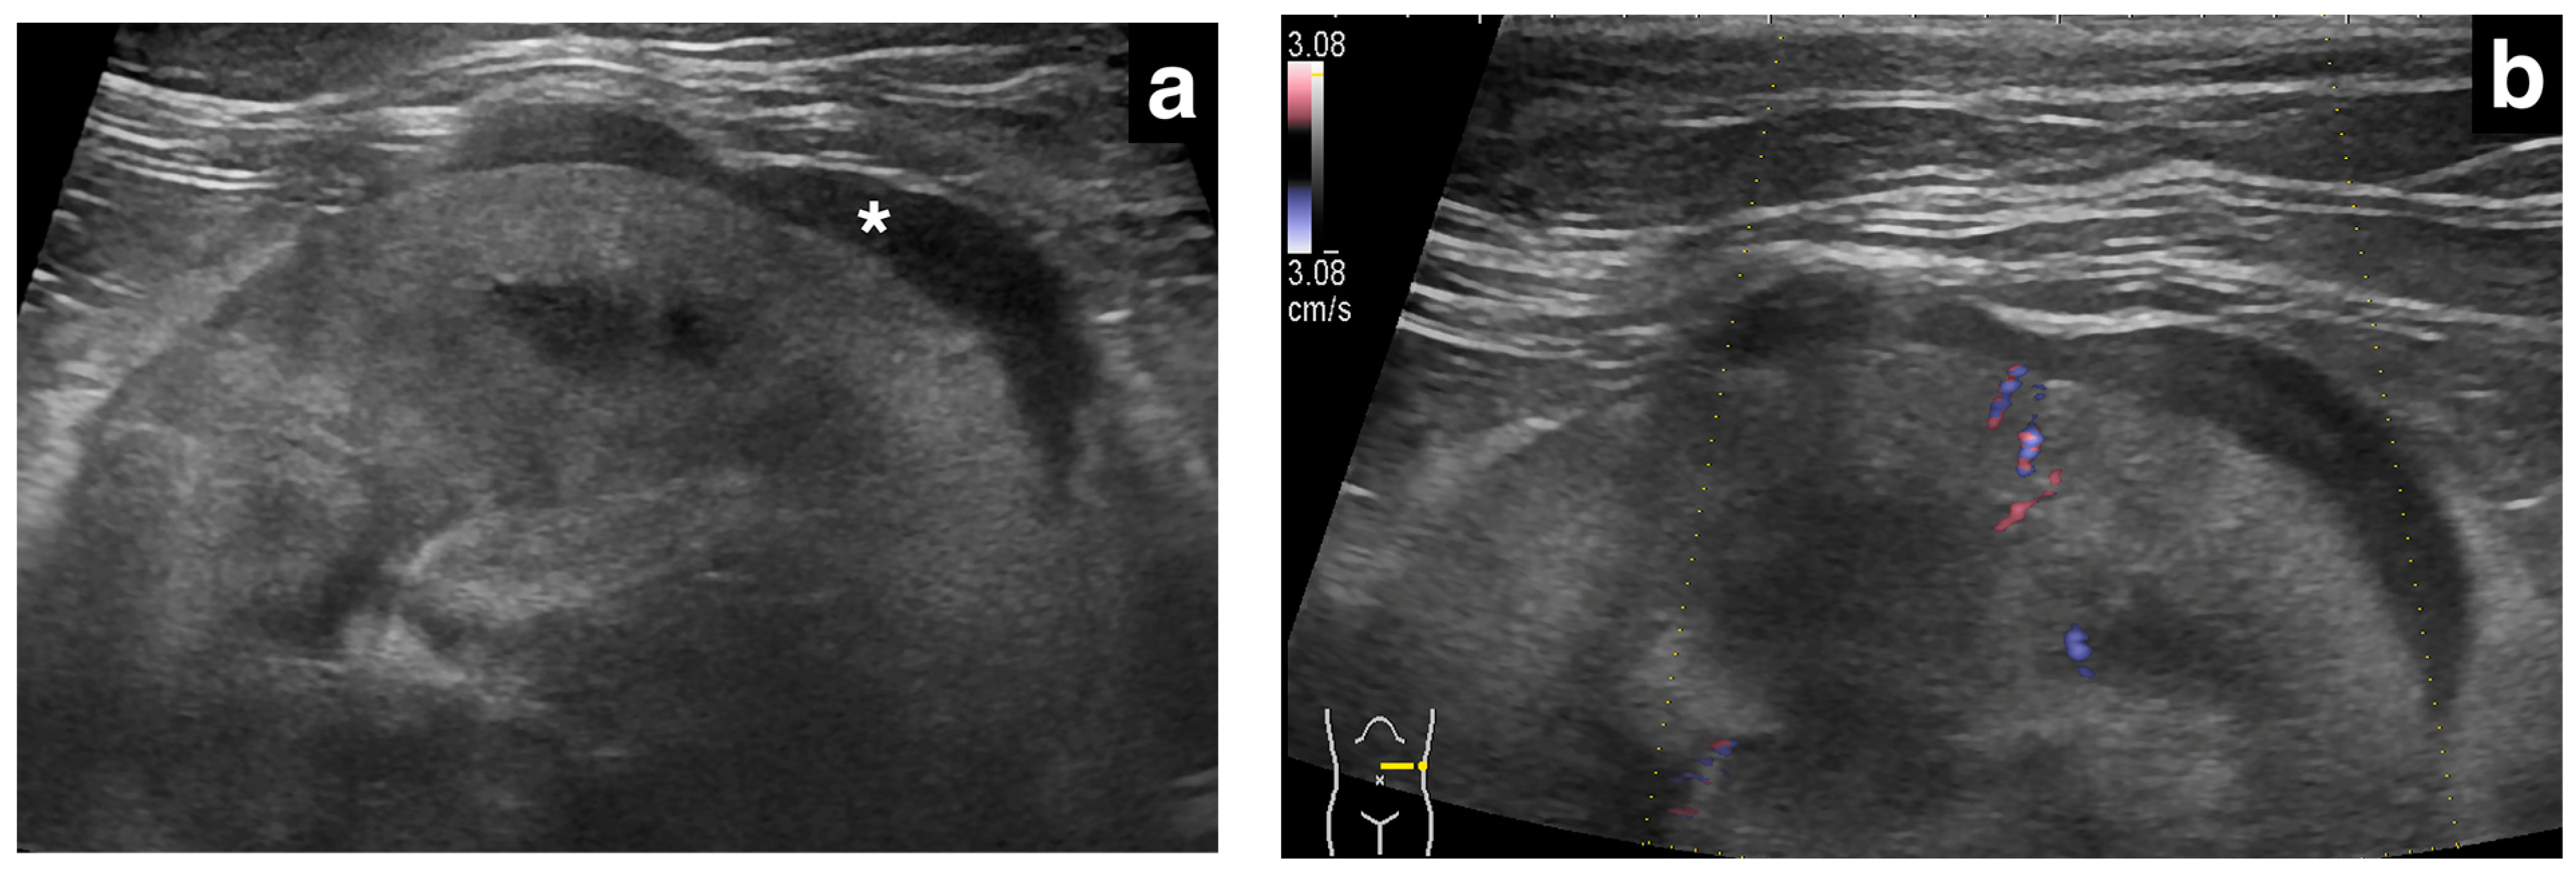

3.3. Ultrasonographic Findings of Subcapsular Thickening

3.4. Ultrasonographic Findings of the Rest of the Kidney

| Distribution | Maximum Thickness (mm) | Echotexture | Echogenicity | Renal Cortical Margin | Renal Capsular Margin | Vascularity | Perirenal Effusion | Architecture | Characteristic Pattern | Corticomedullary Distinction | Renal Pelvis Diameter (mm) | Mineralization | Cystic Lesion | Nodule | |||||

| right | circumferential | 13.2 | hetero | hetero | irregular | irregular | yes | yes | abnormal | completely effaced | 1.9 | yes | yes | no | Primary Renal Carcinoma | ||||